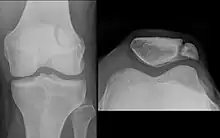

Vertical alignment

A patella alta is a high-riding (superiorly aligned) patella. An attenuated patella alta is an unusually small patella that develops out of and above the joint.

A patella baja is a low-riding patella. A long-standing patella baja may result in extensor dysfunction.[5]

The Insall-Salvati ratio helps to indicate patella baja on lateral X-rays, and is calculated as the patellar tendon length divided by the patellar bone length. An Insall-Salvati ratio of < 0.8 indicates patella baja.[6]